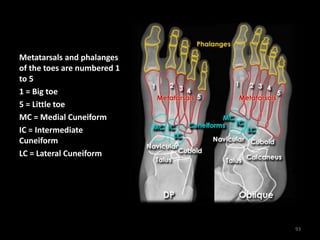

Foot X-ray anatomy - DP

and Oblique views

92

Metatarsals and phalanges

of the toes are numbered 1

to 5

1 = Big toe

5 = Little toe

MC = Medial Cuneiform

IC = Intermediate

Cuneiform

LC = Lateral Cuneiform